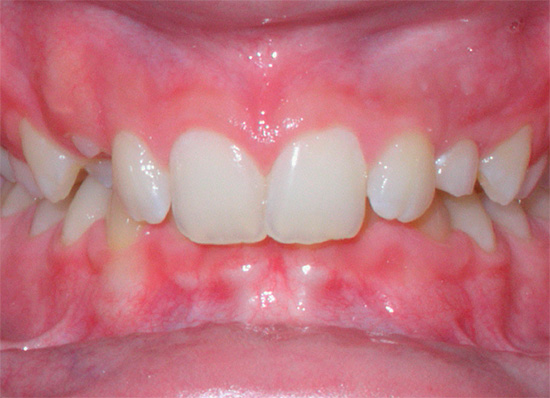

Morso incrociato

Come suggerisce il nome, con un morso incrociato, i denti, chiudendosi, si intersecano.

Con un morso incrociato, c'è una discrepanza nella dimensione delle mascelle nella regione laterale. Gli ortodontisti attribuiscono questo tipo di occlusione a anomalie trasversali e la patologia può essere unilaterale e bilaterale.

La fotografia sotto mostra un esempio di morso incrociato in un adulto: